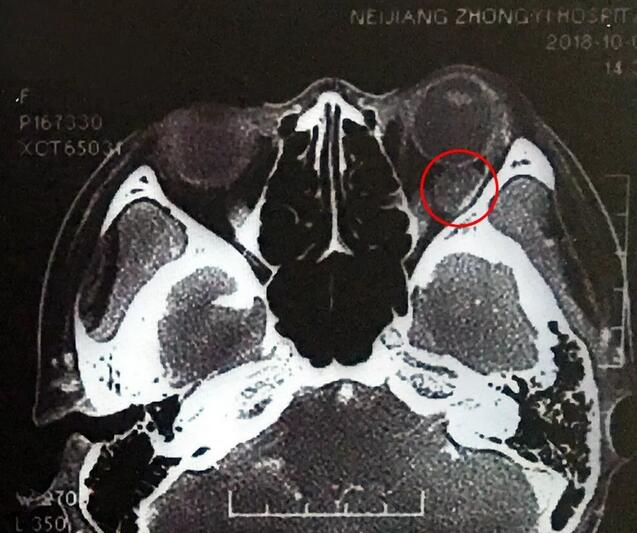

小何是四川南部县人,今年20岁,在内江上大学。今年9月底开始,出现头痛、反复呕吐,吐得连药都吃不下。医生建议小何做了脑部CT,“结果显示左眼眼球后部有个东西,经过进一步检查竟是肿瘤!”这对小何来讲真是个晴天霹雳。

在成都太阳成tyc122cc(中国)集团,经过详细检查,罗清礼教授根据他40余年的丰富经验,判断为淋巴血管瘤。“现在,虽然她双眼的视力都是1.0,但是眼内肿瘤已经接近眼球那么大了,若不及时手术必将失明。”

罗教授介绍,淋巴血管瘤早期症状并不明显,“一般人感冒是不会头痛、呕吐的。小何的感冒非常幸运,她感冒后引起淋巴增生,导致肿瘤内出血,然后引起了头痛、呕吐等症状,让她能够尽早发现了肿瘤。”患者的肿瘤体积较大,位置较深,位于眶间且紧挨着视神经,手术稍有差错,就可能导致患者视力丧失、大出血等情况发生。得知手术风险后,患者和家属表示非常理解并信任罗教授,坚决要求手术医治。